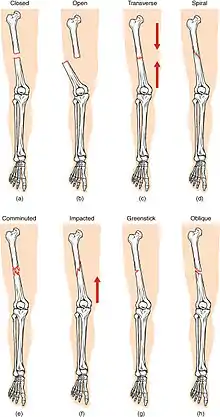

(a) closed fracture

(b) open fracture

(c) transverse fracture

(d) spiral fracture

(e) comminuted fracture

(f) impacted fracture

(g) greenstick fracture

(h) oblique fracture